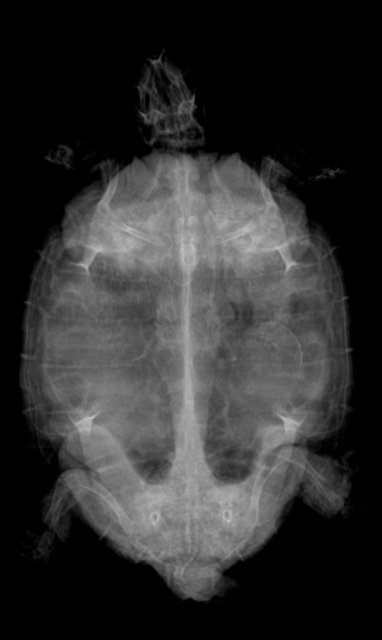

Елена_F Ваше имя: Цып Локация: Россия. г.Курск Опубликовано: 20 марта 2025 Автор Опубликовано: 20 марта 2025 @moth А по рентгену можно что- то сказать? Вроде газов меньше стало.

Консультанты moth Ваше имя: Мария Локация: Москва Опубликовано: 20 марта 2025 Консультанты Опубликовано: 20 марта 2025 @Елена_F врач расшифровку рентгена ещё не делала? по мне лучше стало, но надо чтобы врач смотрела и расшифровала, потому что здесь ошибка будет очень дорого стоить

Елена_F Ваше имя: Цып Локация: Россия. г.Курск Опубликовано: 20 марта 2025 Автор Опубликовано: 20 марта 2025 @moth Расшифровку она не делала, но для сравнения я ей показала старый снимок и она мне показала, что на новом снимке меньше затемнений, т.е. газы уходят. С сердцем тоже вроде всё нормально, осмотрела язык.